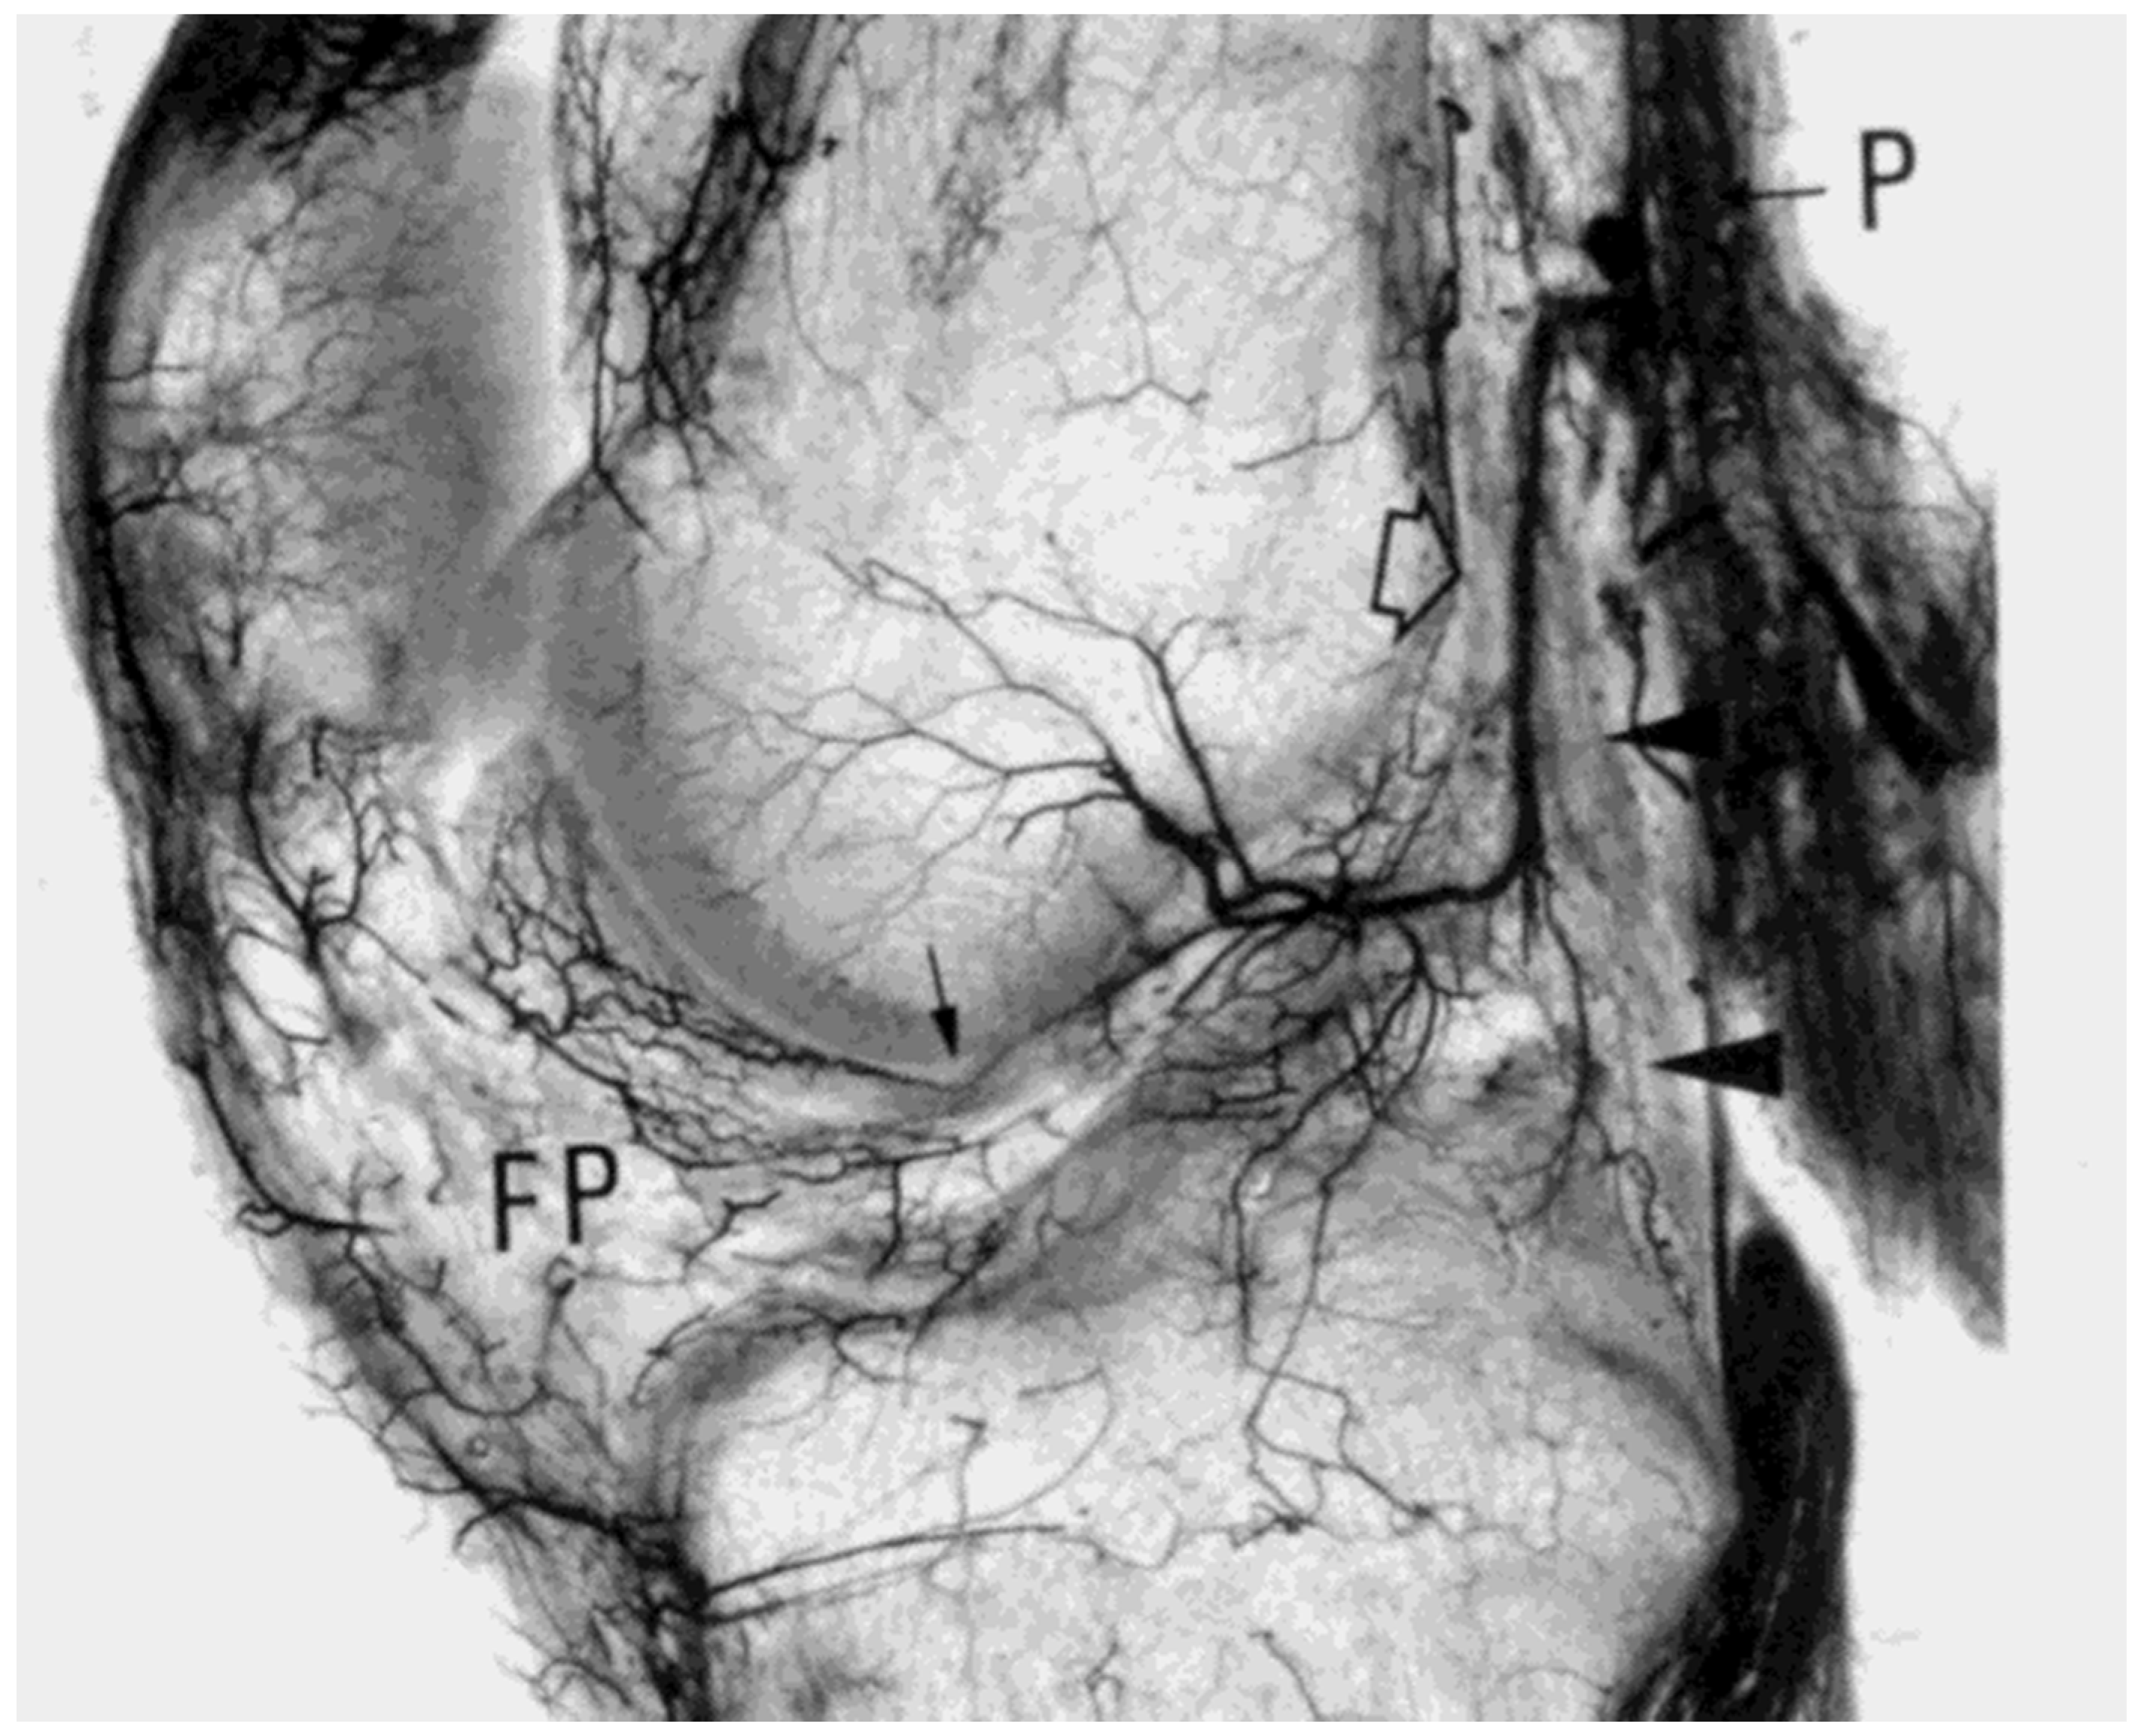

5. Native ACL Blood Supply

- Lin, K.M.; Vermeijden, H.D.; Klinger, C.E.; Lazaro, L.E.; Rodeo, S.A.; Dyke, J.P.; Helfet, D.L.; DiFelice, G.S. Differential regional perfusion of the human anterior cruciate ligament: Quantitative magnetic resonance imaging assessment. J. Exp. Orthop. 2022, 9, 50. [Google Scholar] [CrossRef]

- Scapinelli, R. Vascular anatomy of the human cruciate ligaments and surrounding structures. Clin. Anat. 1997, 10, 151–162. [Google Scholar] [CrossRef]

- Petersen, W.; Hansen, U. Blood and lymph supply of the anterior cruciate ligament: Cadaver study by immunohistochemical and histochemical methods. J. Orthop. Sci. 1997, 2, 313–318. [Google Scholar] [CrossRef]

- Petersen, W.; Zantop, T. Anatomy of the anterior cruciate ligament with regard to its two bundles. Clin. Orthop. Relat. Res. 2006, 454, 35–47. [Google Scholar] [CrossRef] [PubMed]

- Duthon, V.B.; Barea, C.; Abrassart, S.; Fasel, J.H.; Fritschy, D.; Ménétrey, J. Anatomy of the anterior cruciate ligament. Knee Surg. Sports Traumatol. Arthrosc. 2006, 14, 204–213. [Google Scholar] [CrossRef]